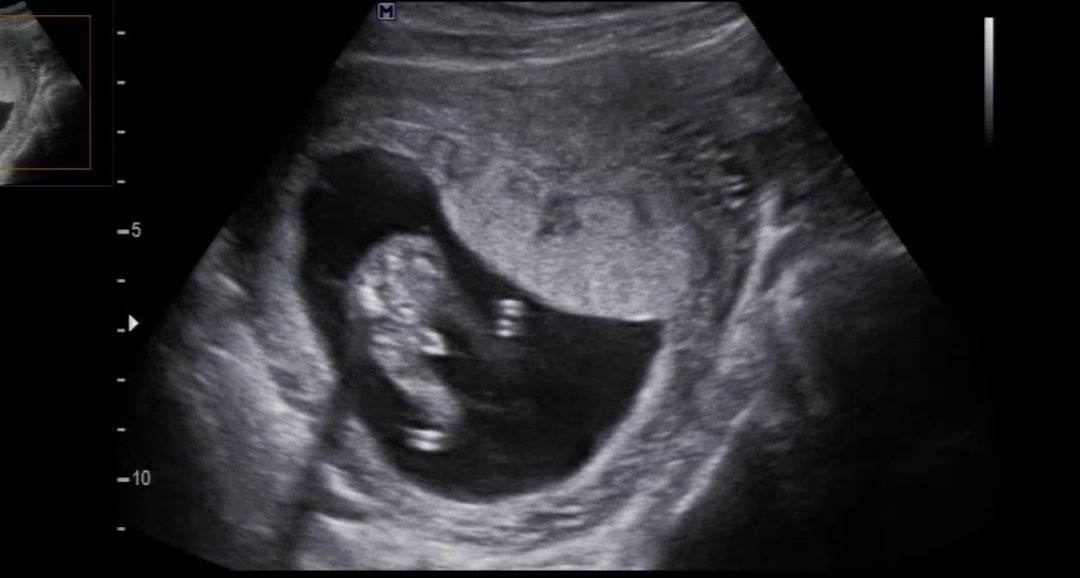

15주 성별 문의

15주차에 초음파 봤어요~ 아기는 엎드려있는 자세를 보여주었고 엉덩이쪽 초음파 봤는데 생식기가 정가운데 있지 않고 살짝 기울어져있는거 같아보여서요! 이게 탯줄인지, 생식기인지 혹시 구분하실수 있으신분 댓글 부탁드립니다ㅠㅠ!! 의사선생님은 아들같다고하시는데 생식기인지 헷갈리네요 ㅋㅋㅋㅋㅋㅋㅋ 혹시 15주차에 성별 확인하고 반전있으셨던분들도 계시면 알려주세요!!!